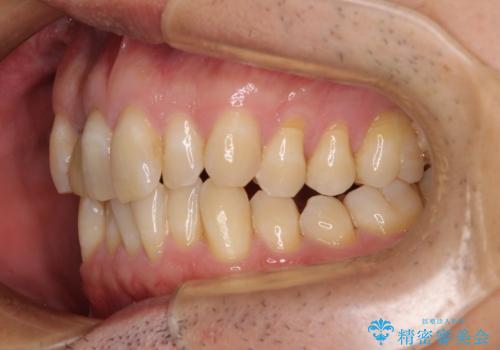

前歯のデコボコを治したい インビザラインによる矯正治療

- 前歯のデコボコを気にして来院された患者様です。

目立たない装置で手軽に治したいとのことで、インビザラインにて矯正治療を行うこととしました。

前歯のクラウンは変色が著しいため、矯正治療後にオールセラミッククラウンにて補綴治療を行うこととしました。

担当医としてはもう少し前歯のデコボコを改善したいところでしたが、患者様としては十分に満足いく歯列であり、マウスピース矯正に飽きてしまったとのことで、治療終了となりました。